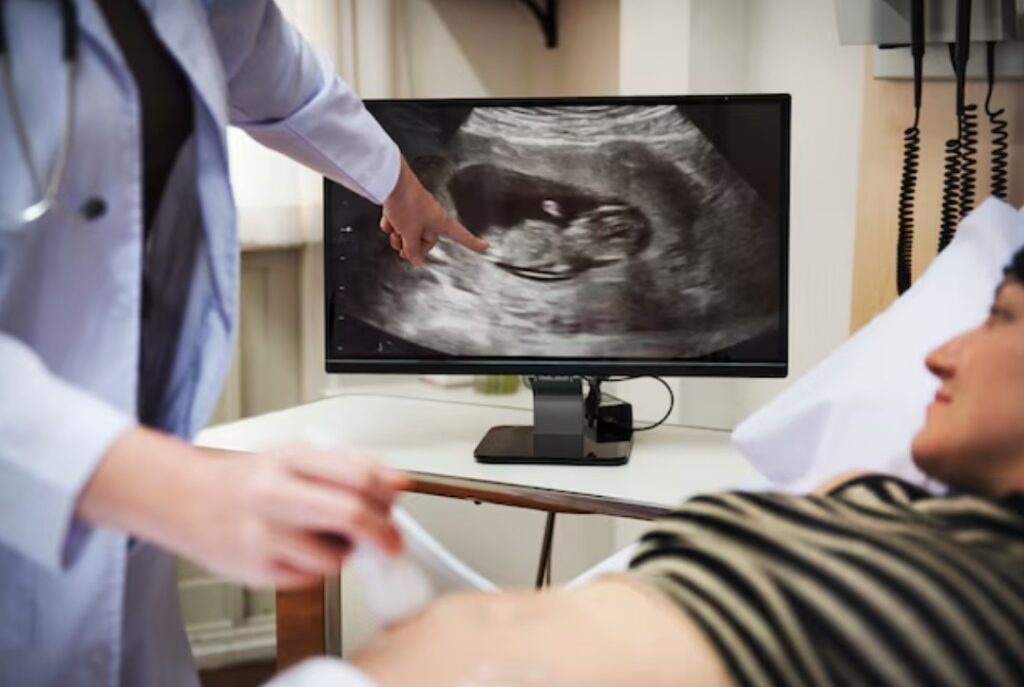

كيف تتم اشعة الحوض المنزلية خطوة بخطوة السونار المنزلي

كيف تتم اشعة الحوض المنزلية خطوة بخطوة

اشعة الحوض المنزلية: دليل شامل للمرضى اشعة الحوض المنزلية أصبحت واحدة من أهم الخدمات الطبية الحديثة التي توفر راحة كبيرة... اقرأ المزيد